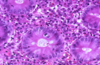

Carcinoid Tumor

Carcinoid Tumor

Carcinoid Tumor